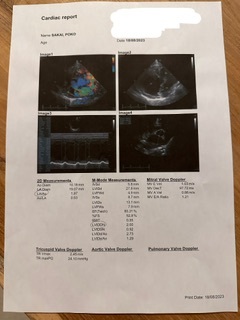

最新のデータです🫀

ぽこの最新のデータです🫀

ぽこは、心臓が今年の4月頃から大きくなって来ました。

心臓がパンパンで、今は沢山のことを我慢させてしまっています😔